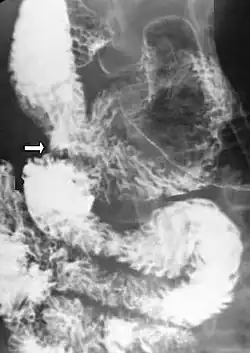

Diagnosis is very difficult, and usually one of exclusion. SMA syndrome is thus considered only after patients have undergone an extensive evaluation of their gastrointestinal tract including upper endoscopy, and evaluation for various malabsorptive, ulcerative and inflammatory intestinal conditions with a higher diagnostic frequency. Diagnosis may follow X-ray examination revealing duodenal dilation followed by abrupt constriction proximal to the overlying SMA, as well as a delay in transit of four to six hours through the gastroduodenal region. Standard diagnostic exams include abdominal and pelvic computed tomography (CT) scan with oral and IV contrast, upper gastrointestinal series (UGI), and, for equivocal cases, hypotonic duodenography. In addition, vascular imaging studies such as ultrasound and contrast angiography may be used to indicate increased bloodflow velocity through the SMA or a narrowed SMA angle.[14][15]

Upper gastrointestinal series showing extreme duodenal dilation (white arrow) abruptly preceding constriction by the SMA.